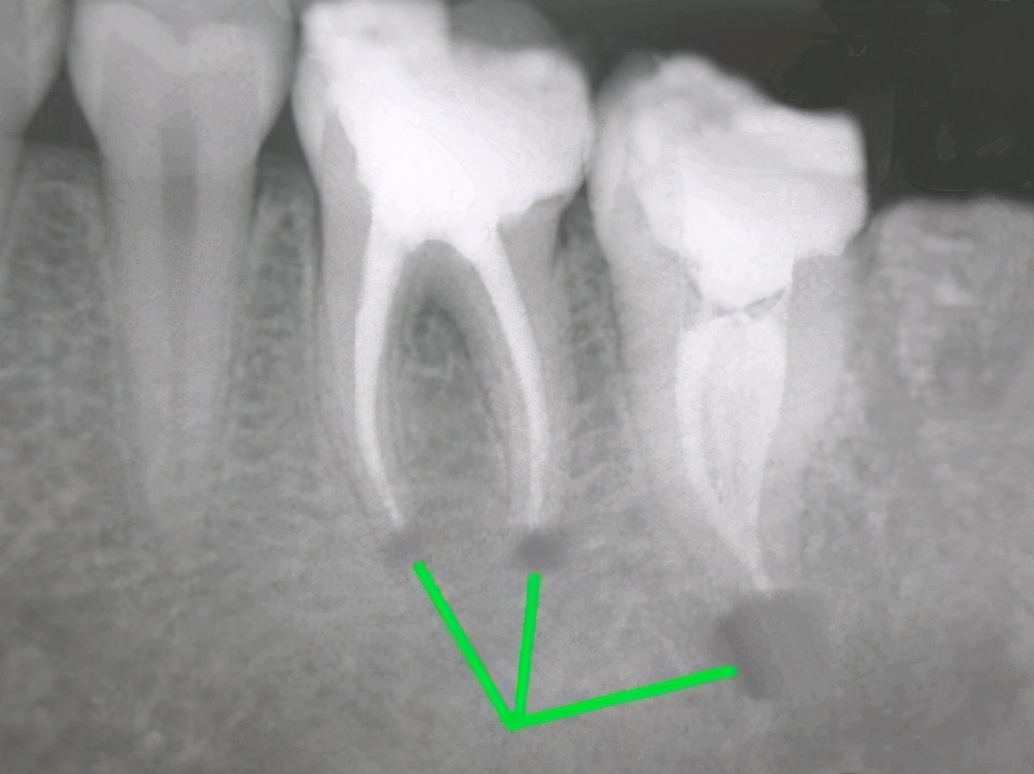

2.牙髓炎引起的牙痛

主要症状:突然剧烈疼痛,没有外部刺激,通常在晚上,或者夜间疼痛比白天更严重,经常疼痛无法入睡,即使您入睡,也会疼得醒来,冷,热刺激会加剧疼痛,患者将无法准确找到哪颗牙齿有问题。您可以使用定下牙痛胶囊,如果无法控制,就必须去医院!